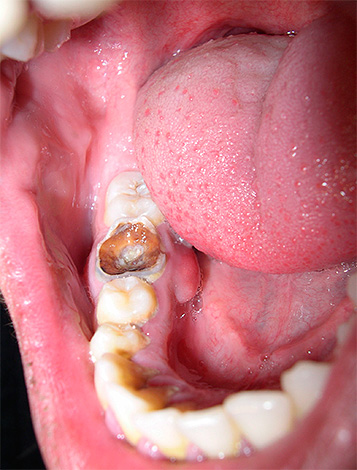

In generale, la pulpite è un'infiammazione del fascio neurovascolare all'interno della corona del dente e dei canali radicolari. Se in alcuni casi di polmonite acuta (focale) è possibile interrompere il processo infiammatorio e trattare il dente in modo conservativo, cioè senza rimozione del nervo, quindi la pulite cronica è quasi sempre una forma irreversibile della malattia. In questo caso, una graduale degenerazione della polpa avviene all'interno del dente: la formazione di tessuto fibroso, la necrosi (necrosi) o la proliferazione del fascio neurovascolare fino a riempire la cavità che porta alla patologia.

Le forme croniche di pulpite sono causate da microrganismi patogeni, nonché dai loro prodotti metabolici, e nella maggior parte dei casi la malattia è provocata dalla carie profonda o da un trattamento improprio: violazione della tecnica di lavorazione del dente, scarsa pulizia della cavità cariata, riempimento mal posizionato, ecc. "Trigger" meno frequenti dello sviluppo della patologia sono:

Poiché la pulpite cronica è una forma irreversibile di infiammazione dei tessuti molli, quando non possono più essere immagazzinati nel dente, vengono spesso utilizzati per il trattamento estrazione completa della polpa da tutti i canali dentali. Lo stesso approccio è seguito nel trattamento della pulpite cronica nella fase acuta.

Nell'odontoiatria moderna, viene data preferenza al metodo di estirpazione (estrazione) vitale del "nervo". Durante il trattamento delle forme croniche di pulpite o delle sue esacerbazioni, viene utilizzata solo l'anestesia senza fondi aggiuntivi per la devitalizzazione (uccisione) della polpa.